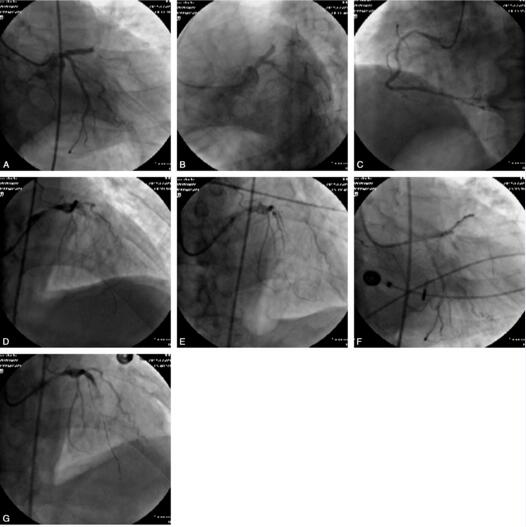

入院查体:血压112/57mmHg心率120次/分,律齐,心音低钝,各瓣膜未闻及杂音。双下肢无水肿。实验室检查:CK 6681U/L、CK-MB 76U/L;肌钙蛋白>4.885ng/ml。血常规示:中性粒细胞百分比77%。入院心电图显示:V1~V4导联ST段呈弓背样抬高,诊断:冠心病,急性前壁心肌梗死,KillpⅠ级。给予冠心病药物强化治疗,效果欠佳,患者胸痛仍反复发作,故急诊行冠脉造影检查。CAG结果:左冠优势型,左主干未见异常,LAD近段闭塞;LCX及RCA未见狭窄。根据造影结果决定开通前降支,以6FJL4.0指引导管置左冠口,送PLIOT 50导丝至前降支远端,送入抽吸导管反复抽吸6次,有大量碎小血栓,故予冠脉内推注替罗非班3ml,再分别以1.5mm×20mm及2.5mm×20mm球囊予以扩张,前向血流TIMI 2级,故先于前降支近段狭窄处置入resolute 3.5mm×30mm支架1枚,压力为10~12atm,造影提示TIMI 1级,支架远端可见夹层,同时患者血压下降至80/50mmHg,立即给予多巴胺升压,并行IABP置入,进行主动脉内球囊反搏,并再次给冠脉内推注替罗非班、腺苷等药物,血流较前改善,故再顺导丝于支架远端置入1枚resolute3.0mm×18mm支架并与前一枚支架连接,压力为10~12atm,此时患者再次出现血压下降,心电监测示加速性室性自主心律。后突然意识丧失,潮式呼吸,心电监测示室颤,立即给予电除颤,并予利多卡因抗心律失常,同时气管插管、升压、扩冠、纠正酸中毒等药物治疗,并持续心外按压等抢救,约1个半小时左右患者心律恢复为窦性,意识恢复,抢救成功,送入ICU进一步观察治疗。病情渐趋平稳,1周后出院。手术经过见图4。

图4 A~C.前降支近段闭塞、第一钝缘支中段70%狭窄;D~G.前降支近段、中段支架置入及支架术后慢血流的发生过程